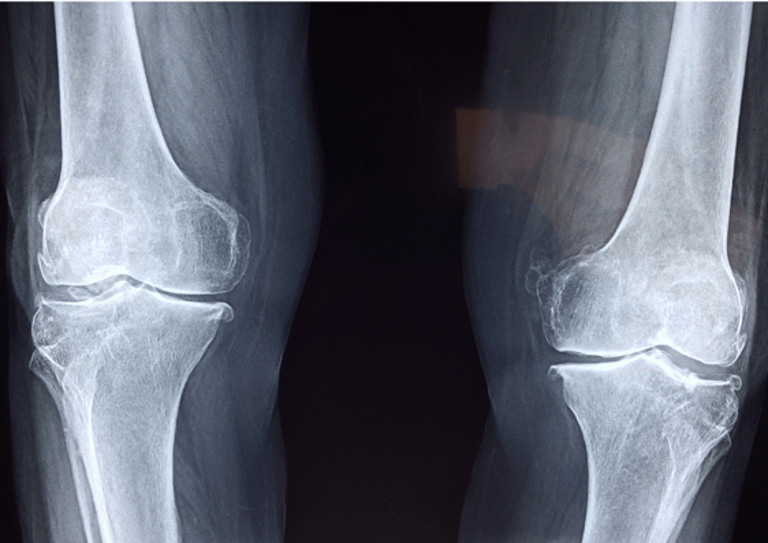

Pediatric Orthopedics

Expert care for bone and joint issues in children, including fractures, deformities, and growth-related conditions.Pediatric Endocrinology

Comprehensive care for juvenile arthritis, lupus, and other autoimmune conditions affecting children’s joints and tissues.Pediatric Gastroenterology & Endoscopy